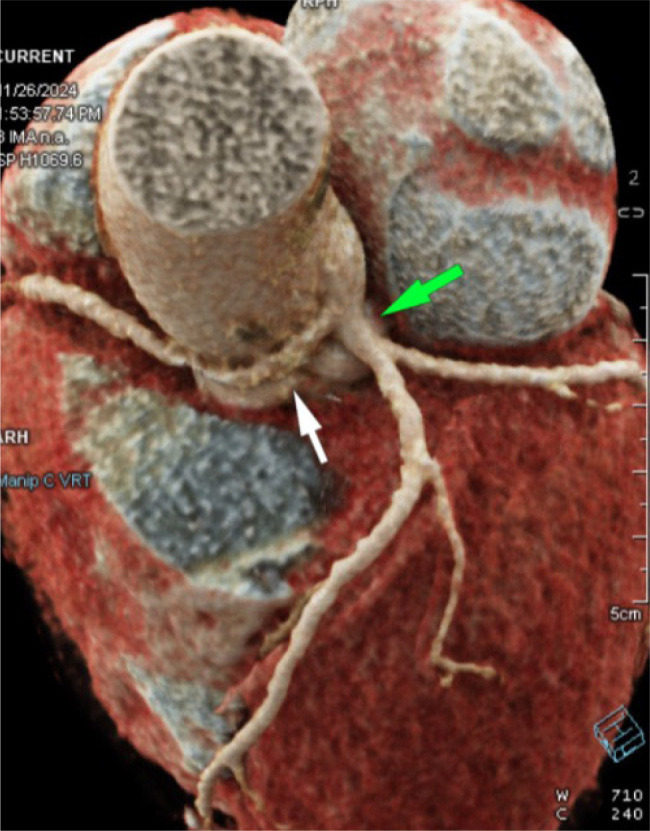

冠状动脉起源异常是一种罕见的先天性疾病,可表现为非特异性胸痛或呼吸短促或无症状。早期识别是至关重要的,因为某些变异与心脏性猝死的高风险有关。在此,我们报告一例53岁女性高血压,甲状腺功能减退,肥胖(II级)和间歇性胸痛放射到左臂两年的病史。心脏科检查包括心电图、心脏酶、超声心动图和CT冠状动脉造影显示右冠状动脉(RCA)起源于左冠状动脉主干(LMCA),但血流动力学上没有明显的狭窄。本病例强调了先进成像技术在评估非典型胸痛中的重要性,它可以揭示冠状动脉的关键先天性异常。虽然该异常与本例患者的缺血无关,但其识别对于适当的管理和风险分层至关重要。学习要点:先进的成像技术在评估非典型胸痛时很重要,它可以显示冠状动脉的关键先天性异常。CT冠状动脉造影仍然是诊断和风险评估的重要工具。尽管本例中右冠状动脉与缺血无关,但持续监测和心血管危险因素管理对于长期预后至关重要。

Anomalous origin of the coronary arteries is a rare congenital condition that can present as non-specific chest pain or shortness of breath or remain asymptomatic. Early identification is critical as certain variants are linked with a high risk of sudden cardiac death. Here, we report the case of a 53-year-old female with hypertension, hypothyroidism, obesity (class II) and a history of intermittent chest pain radiating to the left arm for two years. A cardiology workup including ECG, cardiac enzymes, echocardiography and CT coronary angiography revealed an anomalous origin of the right coronary artery (RCA) arising from the left main coronary artery (LMCA) with no haemodynamically significant narrowing. This case highlights the significance of advanced imaging techniques in evaluating atypical chest pain, which can reveal critical congenital anomalies of the coronary arteries. Although this anomaly was not associated with ischaemia in our patient, its recognition is vital for appropriate management and risk stratification.

Learning points: Advanced imaging techniques are important in evaluating atypical chest pain, which can reveal critical congenital anomalies of the coronary arteries.CT coronary angiography remains an essential tool for diagnosis and risk assessment.Although the right coronary artery was not associated with ischaemia in this case, continued monitoring and cardiovascular risk factor management are essential for long-term prognosis.